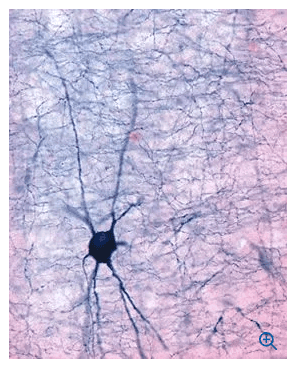

The Leica VT1000 S vibrating blade microtome is the instrument of choice for high-quality sectioning requirements in neurophysiology, neuropathology experimental pathology ), Botany (roots and plants) and Industry (foams).

When sectioning fixed tissue for specific neuropathology tests the Leica VT1000 S consistently provides high-quality sectioning results.